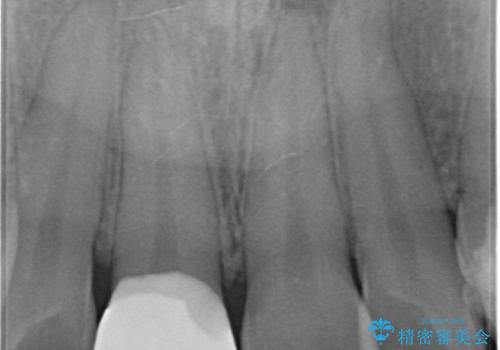

- 前歯のかぶせ物の色が気になるとのことで来院された患者様です。

セラミッククラウンで作り変えていきます。

- 右上1: 仮歯/11,000円、ジルコニアクラウン(スタンダード)/121,000円 合計132,000円(税込)費用は治療当時の料金となります